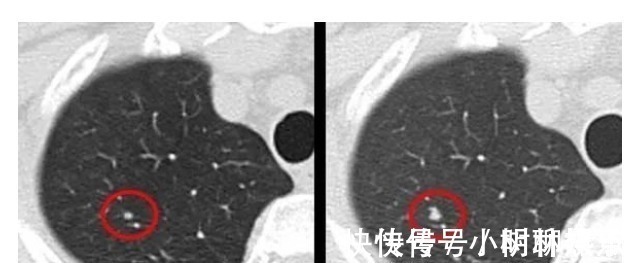

文章插图

肺结节(肺部横截面)

一般年龄大、肺部有基础疾病的人,做检查易发现肺部结节。只有极少部分人最后被证实是肺癌。

检查方式:对于小于5毫米的微小结节,定期观察,3个月到半年重新做一次CT检查,但1厘米以上的大结节,建议要尽早诊治。

★医生建议:40岁以上的人建议做一次低剂量螺旋CT,作为筛查可以发现一些早期肺结节。(关爱父母,陪他们做一次)

★就诊科室:呼吸内科、肺结节诊治分中心。